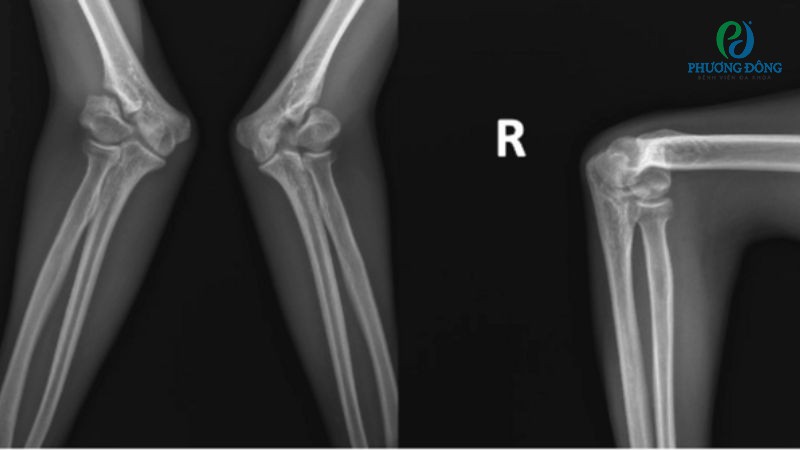

- Chụp X-quang tư thế thẳng và nghiêng nhằm phát hiện tình trạng gãy xương, tổn thương trong cấu trúc xương.